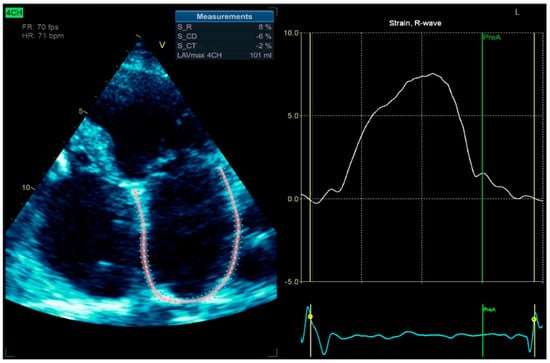

Figure 12.

2D-TTE speckle-tracking strain imaging shows enlargement of the left atrium with an increase in the left atrial volume index (LAVi = 101 mL), demonstrating a loss of contractile phase (−2%) and atrial stunning due to atrial fibrillation.